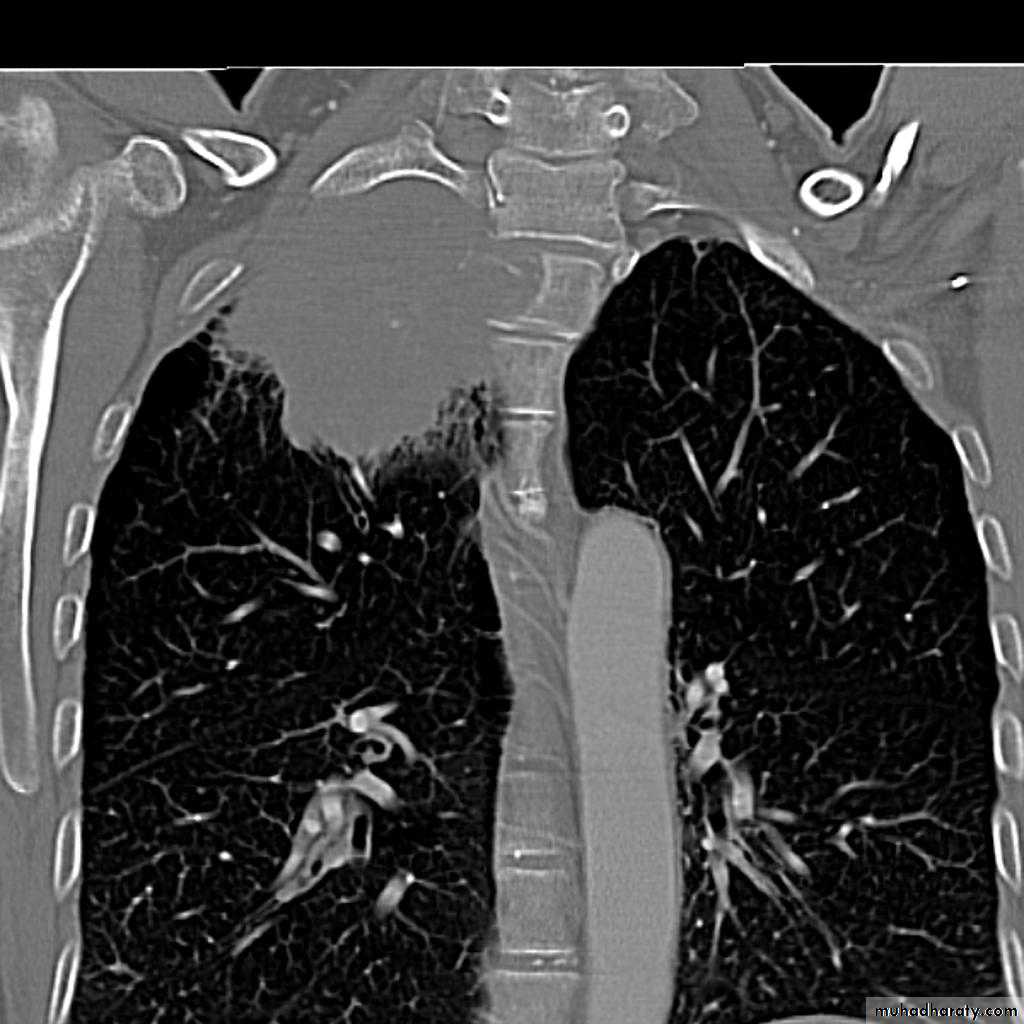

Bronchiactasis

Bronchiectasis refers to abnormal dilatation of the bronchial tree and is seen in a variety of clinical settings. CT is the most accurate modality for diagnosis. It is largely considered irreversibleCauses of bronchiactasias very important to consider

Plain radiograph

Chest x-rays are usually abnormal

1. Tram-track opacities are seen in cylindrical bronchiectasis, and

2. air-fluid levels may be seen in cystic bronchiectasis.

Honey comb shadow

3.Overall there appears to be an increase in bronchovascular markings, and bronchi seen end on may appear as ring shadows .

4.Pulmonary vasculature appears ill-defined, thought to represent peri bronchovascular fibrosis .